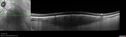

Elmiron (pentasosan polysulfate) Macular Toxicity104 views77 year old female who had been on Elmiron for 20 years and stopped it 2 years agoMar 15, 2026

Elmiron (pentasosan polysulfate) Macular Toxicity89 views77 year old female who had been on Elmiron for 20 years and stopped it 2 years agoMar 15, 2026

Elmiron (pentasosan polysulfate) Macular Toxicity35 views77 year old female who had been on Elmiron for 20 years and stopped it 2 years agoMar 15, 2026

Elmiron (pentasosan polysulfate) Macular Toxicity41 views77 year old female who had been on Elmiron for 20 years and stopped it 2 years agoMar 15, 2026

Elmiron (pentasosan polysulfate) Macular Toxicity45 views77 year old female who had been on Elmiron for 20 years and stopped it 2 years agoMar 15, 2026

Elmiron (pentasosan polysulfate) Macular Toxicity46 views77 year old female who had been on Elmiron for 20 years and stopped it 2 years agoMar 15, 2026

Elmiron (pentasosan polysulfate) Macular Toxicity38 views77 year old female who had been on Elmiron for 20 years and stopped it 2 years agoMar 15, 2026

Elmiron (pentasosan polysulfate) Macular Toxicity37 views77 year old female who had been on Elmiron for 20 years and stopped it 2 years agoMar 15, 2026

Elmiron (pentasosan polysulfate) Macular Toxicity36 views77 year old female who had been on Elmiron for 20 years and stopped it 2 years agoMar 15, 2026

Elmiron (pentasosan polysulfate) Macular Toxicity40 views77 year old female who had been on Elmiron for 20 years and stopped it 2 years agoMar 15, 2026